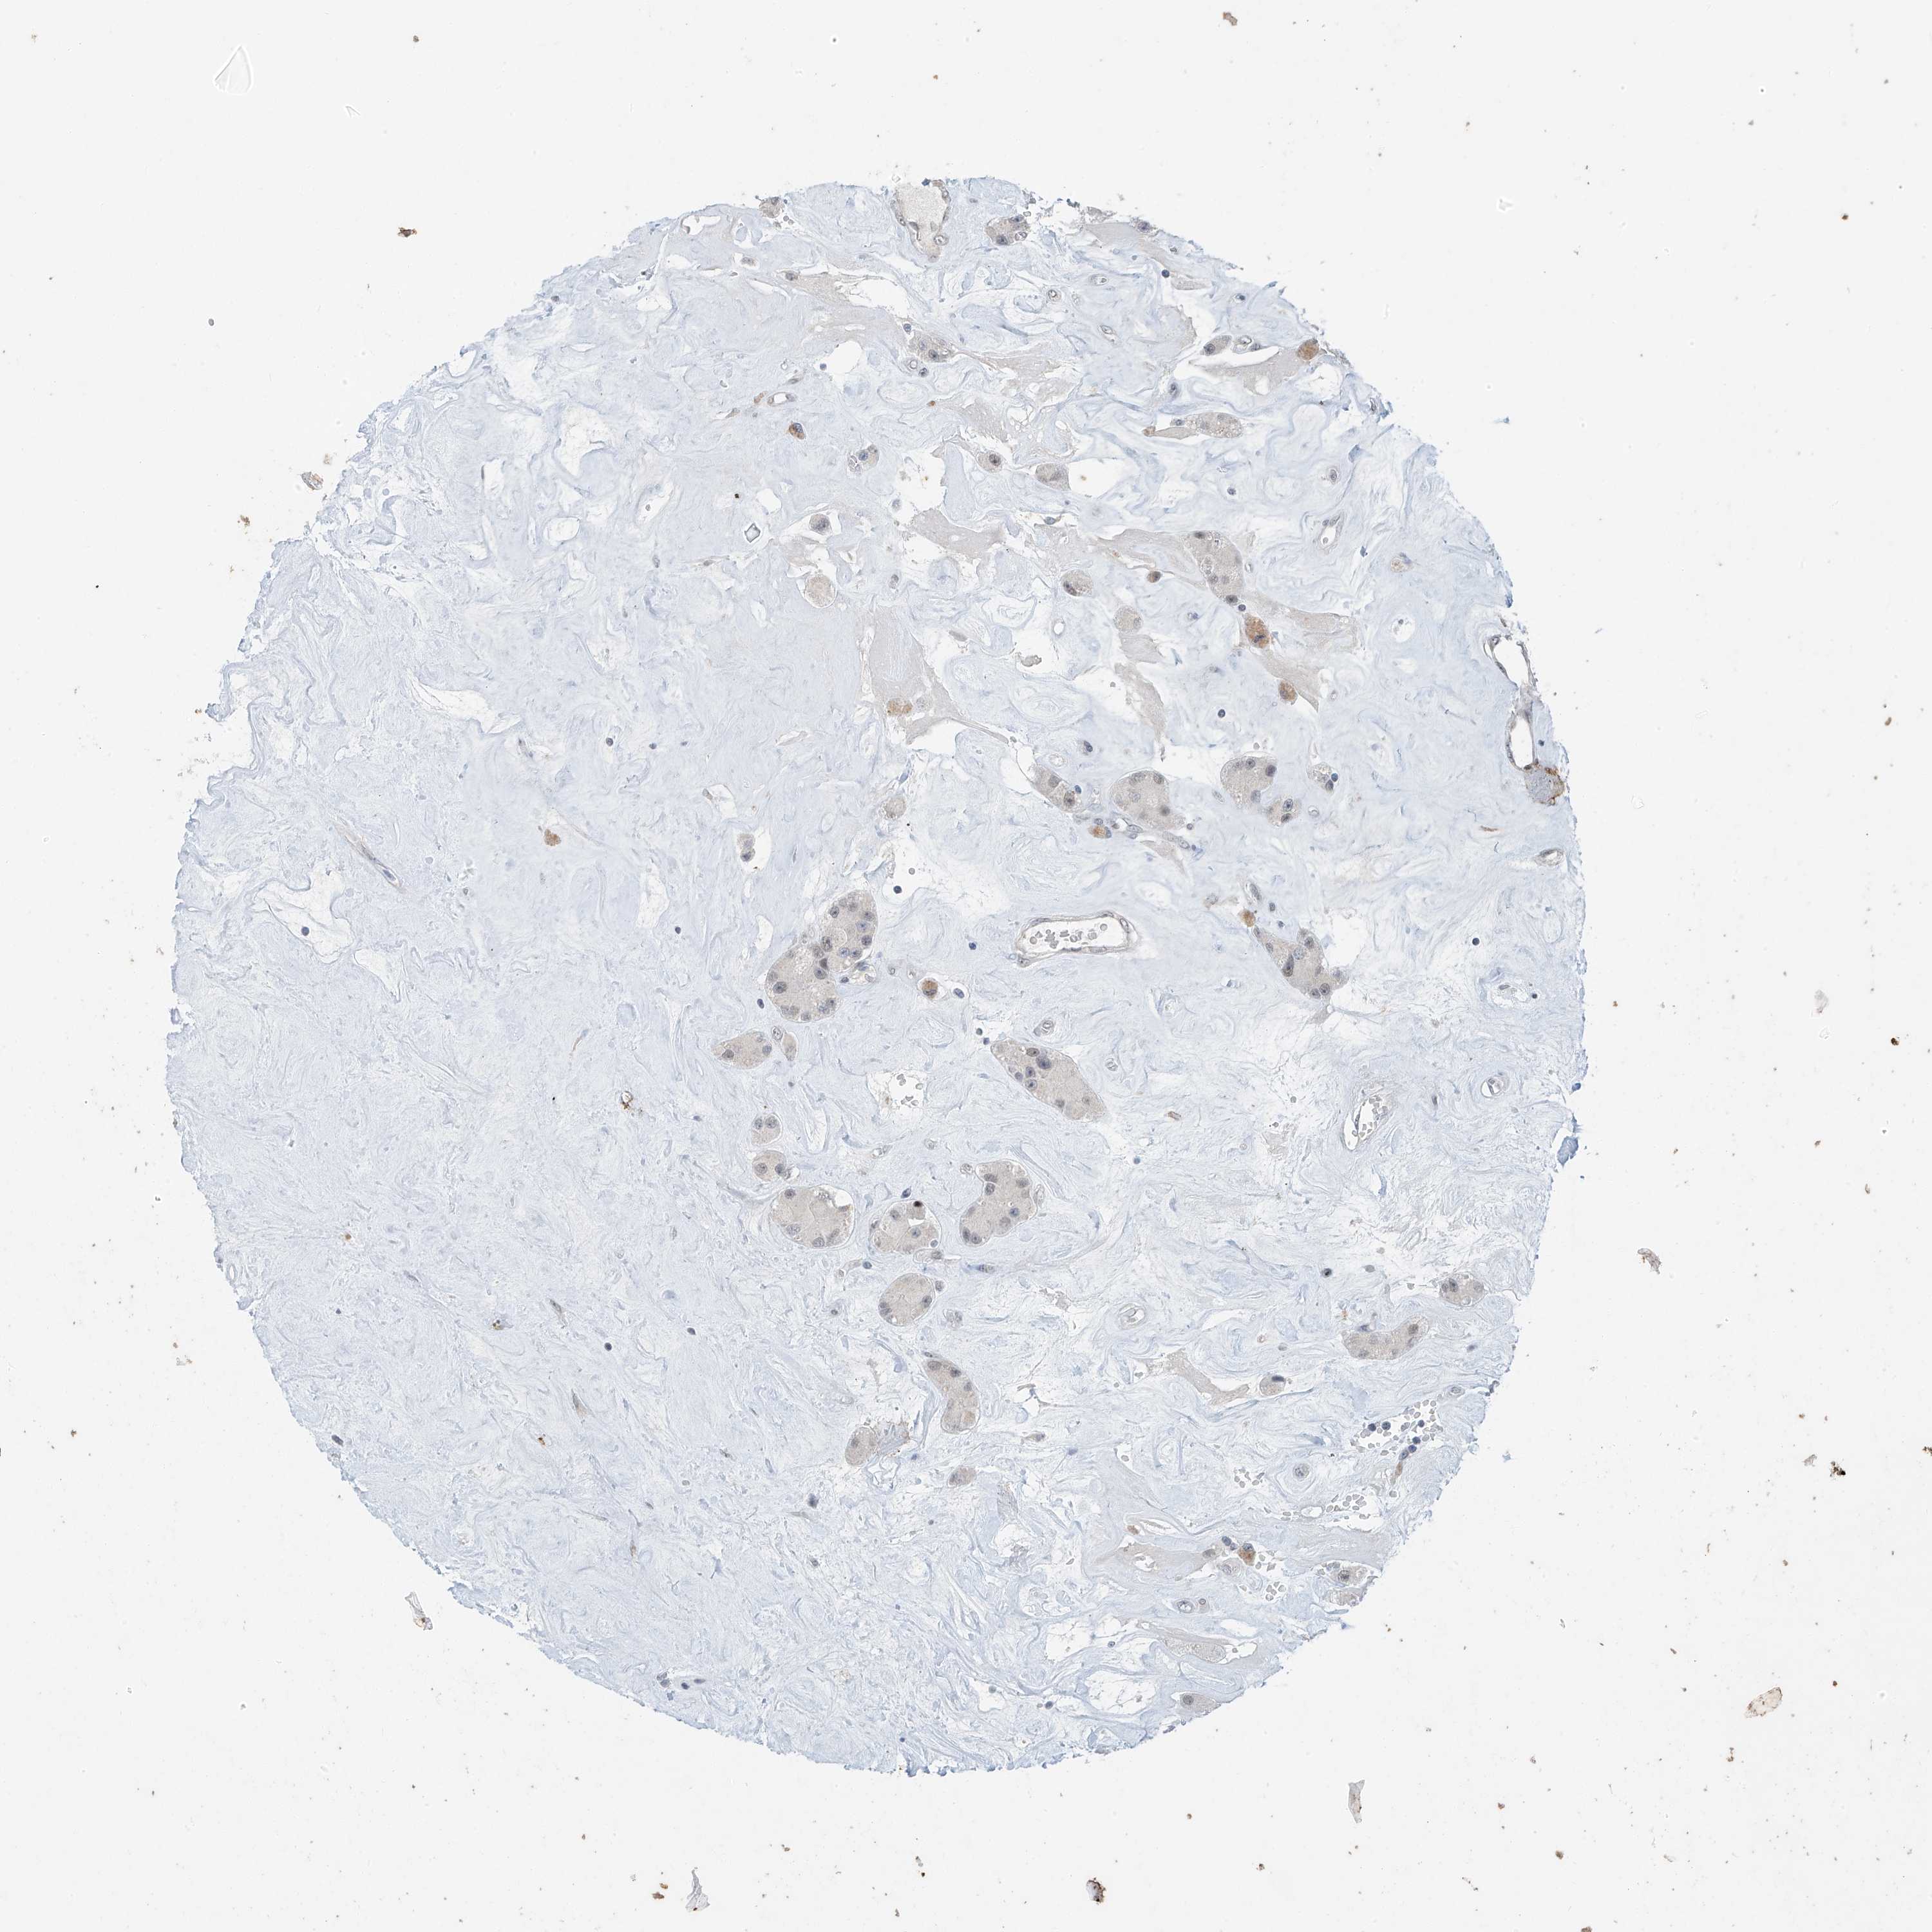

CARCINOID - Protein expressioni

A mouse-over function shows sample information and annotation data. Click on an image to view it in a full screen mode. Samples can be filtered based on level of antibody staining by selecting one or several of the following categories: high, medium, low and not detected. The assay and annotation is described here.

Each image is clickable and will lead to virtual microscopy that enables deeper exploration of all samples and also displays staining intensity scores, fraction scores and subcellular localization as well as patient and tissue information for each sample.

Antibody HPA031731

Staining

High

Medium

Low

Not detected

Intensity

Strong

Moderate

Weak

Negative

Quantity

>75%

75%-25%

<25%

None

Location

Nuclear

Cytoplasmic/membranous

Cytoplasmic/membranous,nuclear

Carcinoma, NOS